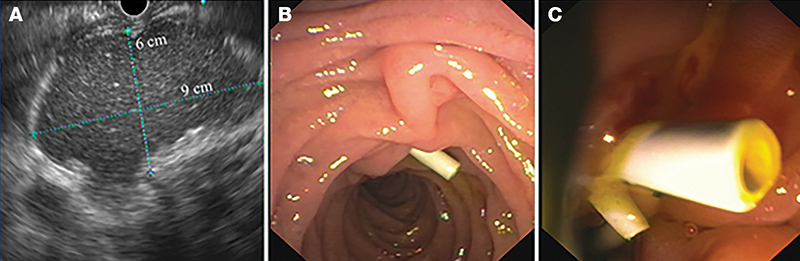

Az endoszkópos kezelések öt esetben jártak terápiás sikerrel; több betegnél különböző típusú endoszkópos eljárás kombinációjára volt szükség. A terápiás eszköztárban szerepelt az endoszkópos retrográd kolangiopankreatográfia (ERCP) során végzett törmelékextrakció, ballonos epeúti dilatáció és stentimplantáció (7. ábra). Ezenfelül endoszkópos ultrahang (EUS) által vezérelt tályogdrenázs is történt.

(A) A gyomor mögött 3 mm-es falú WON (60×90 mm); (B–C) Műanyag stentek a Vater-papillában